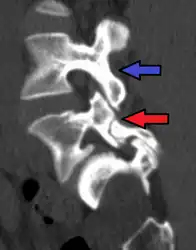

Grade 1 retrolistheses of C3 on C4 and C4 on C5

A retrolisthesis is a posterior displacement of one vertebral body with respect to the subjacent vertebra to a degree less than a luxation (dislocation). Retrolistheses are most easily diagnosed on lateral x-ray views of the spine. Views, where care has been taken to expose for a true lateral view without any rotation, offer the best diagnostic quality.

Retrolistheses are found most prominently in the cervical and lumbar region, but can also be seen in the thoracic area.